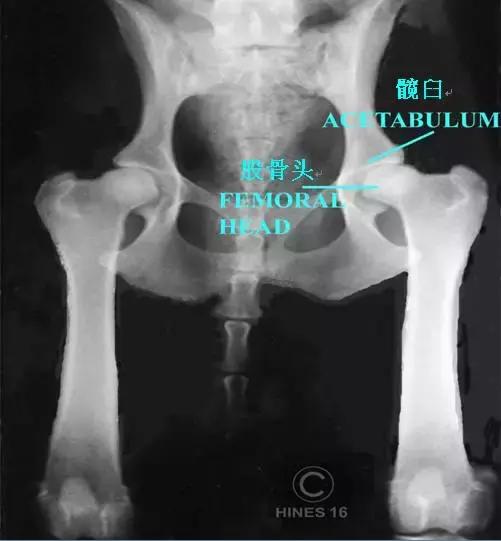

髋关节是连接大腿和骨盆的关节,也是狗全身受力最重的关节。髋关节由球状的股骨头和碗状的髋臼构成,这两个部位形成牢固的结构,使股骨头能够在髋臼中稳定地旋转(话说人也有髋关节,就是连接大腿跟躯干的关节部位)。

股骨头和髋臼之间有平滑的软骨覆盖,并有关节液使摩擦降低至最小,而且还有韧带加强支撑。

图左:正常髋关节,图右:发育不良的髋关节